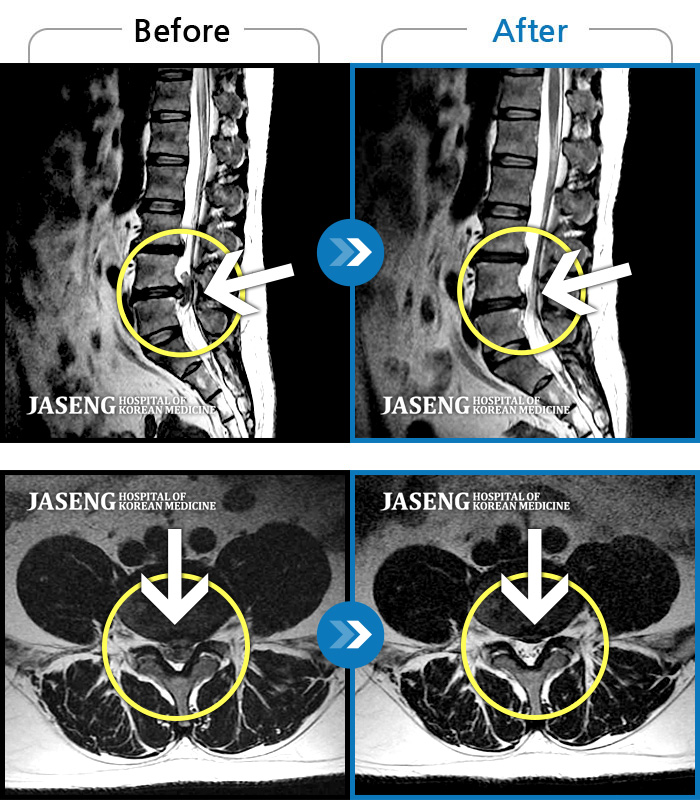

푸쉬업을 여러 번 반복한 뒤 극심한 하요부 통증 및 우측 하지부 저림

2024.03.21 ~ 2024.09.23